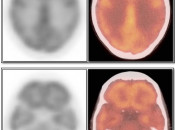

Brain

As the brain fully relies on glucose metabolism, it demonstrates rather diffuse intense uptake of FDG. In fact, its metabolic activity is so intense, that most PET reading software programs will require the reader to manually decrease its intensity to evaluate the brain for potential lesions.

Familiarity with the normal symmetric uptake of FDG in the brain will help the reader identify primary brain tumors and metastatic lesions.

Areas of normal relative increased uptake include the grey matter, basal ganglia, frontal eye fields, posterior cingulate gyrus and visual cortex. Symmetry of uptake should be preserved.